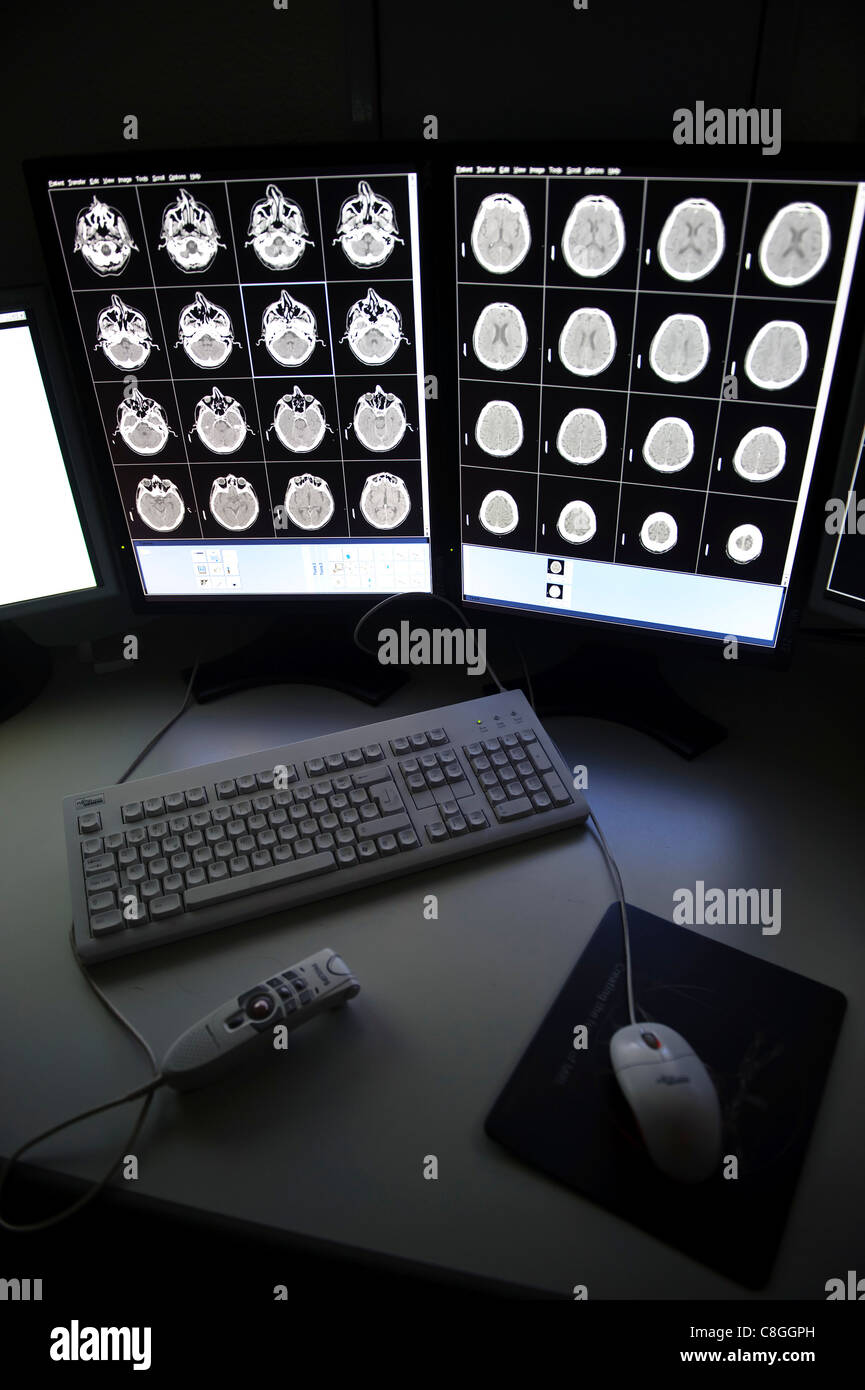

CT scan cérébral sur les écrans d'ordinateur Banque D'Imageshttps://www.alamyimages.fr/image-license-details/?v=1https://www.alamyimages.fr/photo-image-ct-scan-cerebral-sur-les-ecrans-d-ordinateur-39702393.html

CT scan cérébral sur les écrans d'ordinateur Banque D'Imageshttps://www.alamyimages.fr/image-license-details/?v=1https://www.alamyimages.fr/photo-image-ct-scan-cerebral-sur-les-ecrans-d-ordinateur-39702393.htmlRMC8GGPH–CT scan cérébral sur les écrans d'ordinateur